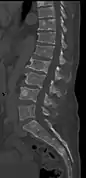

The diagnostic examination of a person with suspected multiple myeloma typically includes a skeletal survey. This is a series of X-rays of the skull, axial skeleton, and proximal long bones. Myeloma activity sometimes appears as "lytic lesions" (with local disappearance of normal bone due to resorption) or as "punched-out lesions" on the skull X-ray ("raindrop skull"). Lesions may also be sclerotic, which is seen as radiodense.[70] Overall, the radiodensity of myeloma is between −30 and 120 Hounsfield units (HU).[71] Magnetic resonance imaging is more sensitive than simple X-rays in the detection of lytic lesions, and may supersede a skeletal survey, especially when vertebral disease is suspected. Occasionally, a CT scan is performed to measure the size of soft-tissue plasmacytomas. Nuclear Medicine Bone scans are typically not of any additional value in the workup of people with myeloma (no new bone formation; lytic lesions not well visualized on nuclear bone scan).